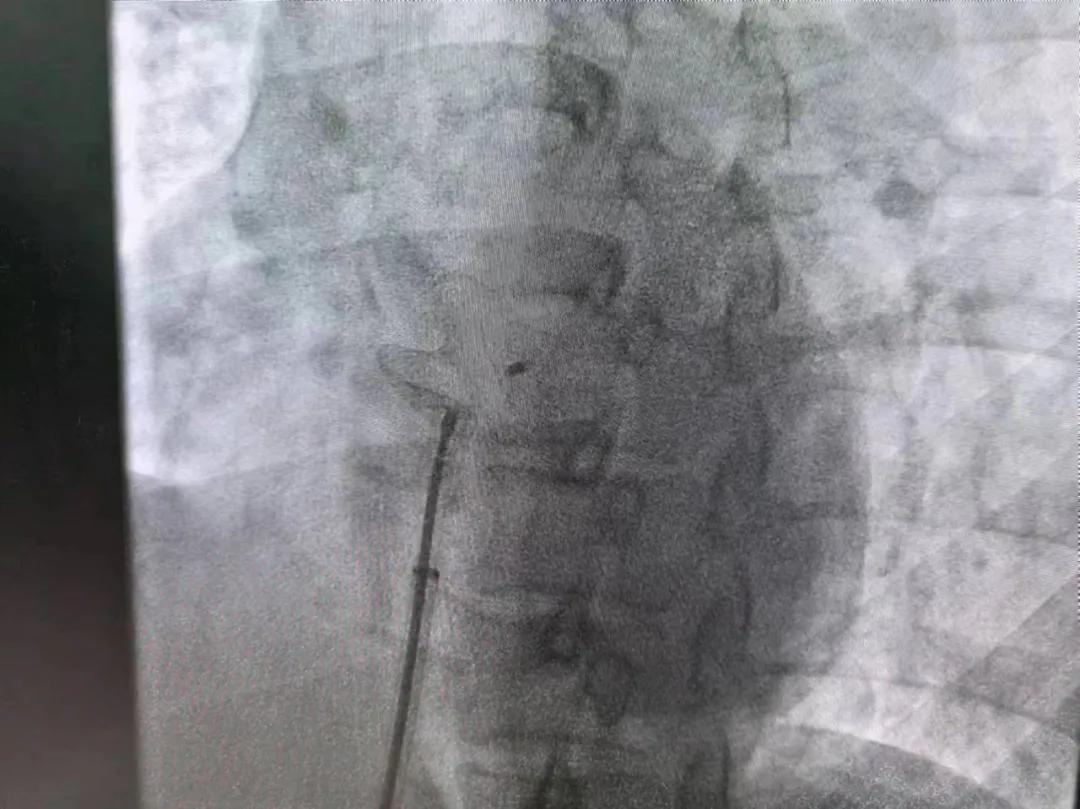

市二院:先天性心臟病介入診療 再創佳績

繼3月14日市二院成功開展首例卵圓孔未閉介入封堵術之后,3月21日上午,市二院院長王瑾及心血管內科主任李慧新帶領心血管內科介入團隊,再次成功為患者實施“經皮房間隔缺損封堵術”,手術過程順利。該例病人的成功手術及康復,標志著市二院心血管內科在結構性心臟病介入診療中再次達到了新高度。

患者為中年女性,41歲,近2年一直反復出現頭暈、頭痛,曾先后在多家醫院就診。近期患者癥狀加重,出現活動后氣喘合并胸悶癥狀,來到心血管內科就診。經心臟彩超檢查顯示:患者房間隔下段連續性中斷,缺損直徑達到了13mm,肺動脈壓已經輕度增高,確診為房間隔缺損。

對于房間隔缺損面積較大的患者,如果長時間不注意,不及時介入封堵治療,心功能可能會出現嚴重問題,一旦出現嚴重肺動脈壓高壓及心力衰竭,將喪失診療機會,會嚴重降低患者生活質量,且極大縮短患者壽命。

于是,院長王瑾會診后,詳細詢問患者病史,認真分析臨床癥候群并準確診斷,耐心做好患者及家屬病情告知和充分溝通。經過完善的術前評估及準備,心血管內科介入團隊成功為患者實施“經皮房間隔缺損封堵術”,手術過程順利。近日,患者已順利康復出院。 (尹紅婭 潘長林)